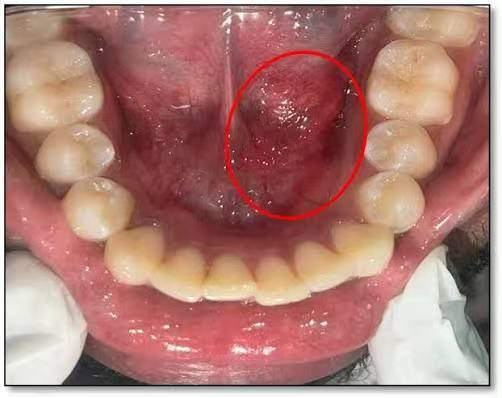

经过详细检查,口腔医学中心魏明波医生发现杨女士左侧颌下腺导管口红肿,按压时唾液分泌明显减少,颌下腺彩超显示腺体增大。结合临床表现,确诊其为因导管狭窄引起的「慢性阻塞性颌下腺炎」。

「这种疾病也是口腔常见病之一,主要表现为与进食相关的颌下区肿胀和疼痛,」魏明波主任解释说,「多数由导管狭窄、结石等局部因素引起,当腺体出现急性化脓性感染时,会出现更严重的症状。」

在详细了解病情与治疗方案后,杨女士接受了抗感染治疗。待炎症控制后,医疗团队每日为她行左侧颌下腺导管疏通,并嘱咐她多进食酸性食物促进唾液分泌。经过数日精心治疗,其左侧口底及颌下区肿痛明显好转。